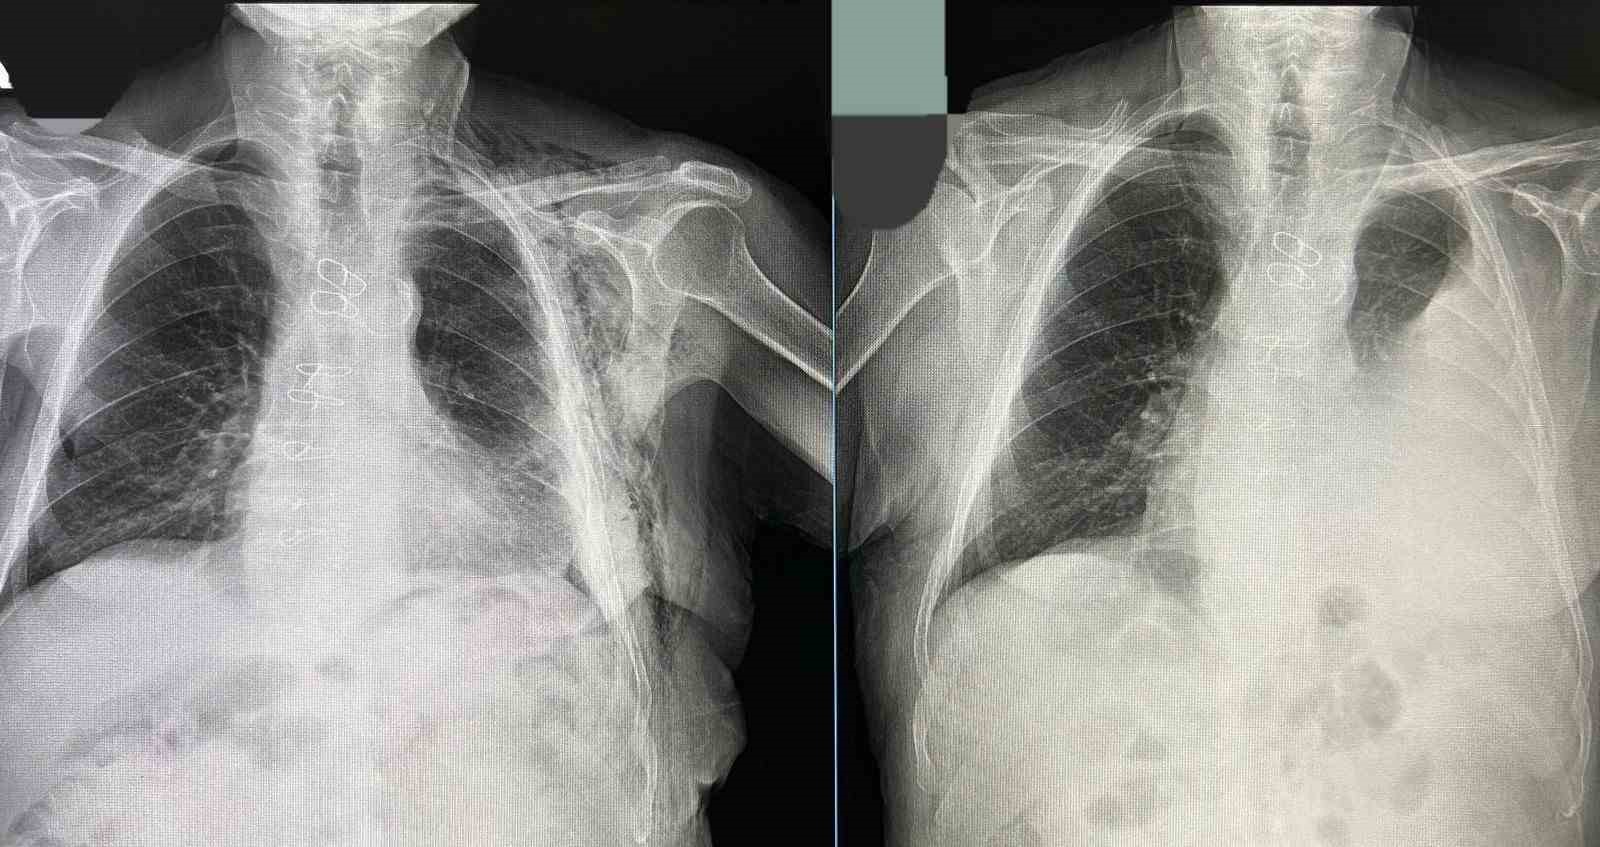

Bayburt Devlet Hastanesinde bir hastaya kapalı yöntemle akciğer ameliyatı yapıldı. 80 yaşındaki hasta, geçirdiği operasyonun ardından sağlığına kavuştu.

Bypass ameliyatı sonrası Göğüs Cerrahisi Polikliniğine kontrole giden hastanın göğüs boşluğunda sıvı biriktiği tespit edildi.

Tüp torakostomiye dirençli efüzyon nedeniyle değerlendirmeye alınan hastaya Göğüs Cerrahisi Uzmanı Op. Dr. Halil Kolcu tarafından kapalı yöntemle akciğeri serbestleme ameliyatı yapıldı.

Başarılı geçen operasyonla hastanın akciğerinin yeniden genişlemesi sağlanırken, sıvı birikiminin önüne geçildi. Hastanın ameliyat sonrası sürecinin sorunsuz ilerlediği ve altıncı günde taburcu edildiği öğrenildi.